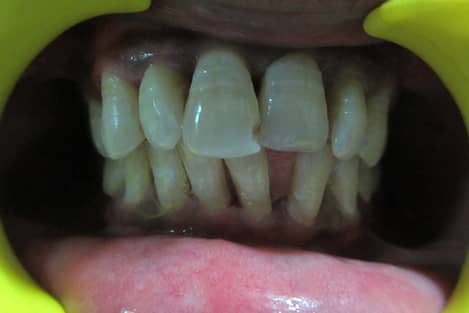

Vital Teeth Bleaching